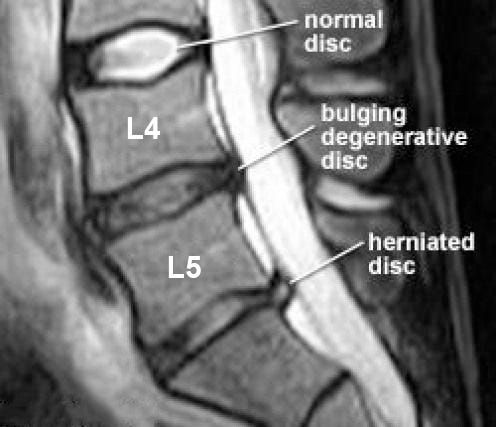

In the case of a bulging disc, the gooey nucleus seeps out into the fibrous annulus - yet the annulus remains intact. For a herniated disc - the annulus ruptures and the nucleus escapes the disc completely.

As you may have guessed - a herniated disc is much more severe than a bulging disc, but in both cases - the athlete will likely experience pain when the spine is flexed or extended (depending where the bulge is), pain under compression and “neural” symptoms.

These neural symptoms are defined by localised pain, numbness or tingling around the injured area or pain further afield.

In many cases, a bulging or herniated disc may compress the adjacent nerve root, which elicits pain downstream of that nerve. For example, a bulging disc in the lumbar spine may cause “sciatica” - numbness, tingling, pain and (in more severe cases) muscle weakness in the leg. These symptoms will occur on the same side of the body as the disc issue - i.e right sided disc bulge = right sided sciatica.